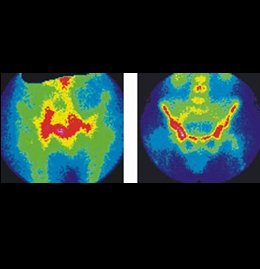

Gamma Ósea Osteoarticular DC/Sacroileitis

¿Has tenido fracturas y continuas con dolor en el área afectada después de varios meses?

¿Tuviste caries dental y ahora te duele el fémur?

¿Tienes dolor en el brazo o pie sin causa aparente?

Este examen te puede ayudar.

Detalle técnico

Se realiza con difosfonatos unidos al Tc99m los cuales se unen a los cristales de hidroxiapatita del hueso. Su captación depende del flujo sanguíneo y de la tasa de neo formación ósea, se usa para descartar infección en hueso (osteomielitis).

Leucocitos marcados in vitro e in vivo. Útil para ver exactamente el sitio de infección.